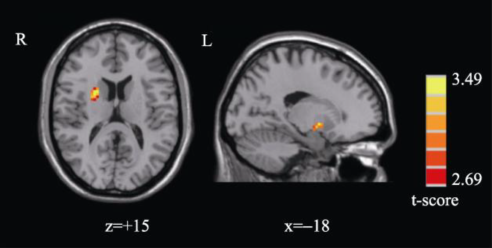

图3 持球条件下激活较大脑区

研究结果包括两个方面:运动表象过程中运动技能水平越高,时间一致性越好,镜像神经系统激活越大;躯体感觉输入调节不同运动技能水平被试运动表象过程中镜像神经系统的激活程度,表现为有躯体感觉输入的情况下,运动员镜像神经系统激活程度较低。